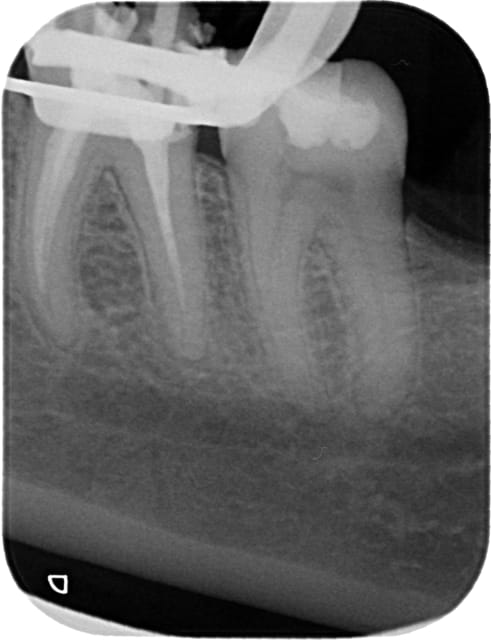

J'ai réalisé l'endo de cette 36 il y a 4 ans et je ne suis pas allé à l'apex, patiente angoissée et douleurs (bref j'ai fait un compromis).

La dent est totalement asymptomatique depuis 4 ans (la pano date d'il y a deux mois).

Vous feriez une RTE avant inlay ?

la radio est un examen complémentaire mais c'est la clinique qui prime. aucune symptomatologie sur la 36 donc aucune raison de refaire l'endo que tu as d'ailleurs faite toi même, sous digue et du mieux que tu as pu. qu'est ce qui te dit que cette fois tu vas faire mieux ? que tu vas pas péter un instrument en voulant désobturer le thermafil ? etc...le mieux est l'ennemi du bien !

pour la 46, même remarque et même attitude. y a t il une raison CLINIQUE au RTE ?? une douleur ? une sensibilité quelqueconque ? une desmodontite ? je ne vois pas d'épaississement ligamentaire notoire et la couronne me semble impeccable. certes j'ai vu l'image apicale, mais qu'est ce qui te dit que cette image est pathologique (ça peut être une image cicatricielle). donc si pas de symptomatolgie, surveillance radiologique et si rien n'évolue : wait and see !!!